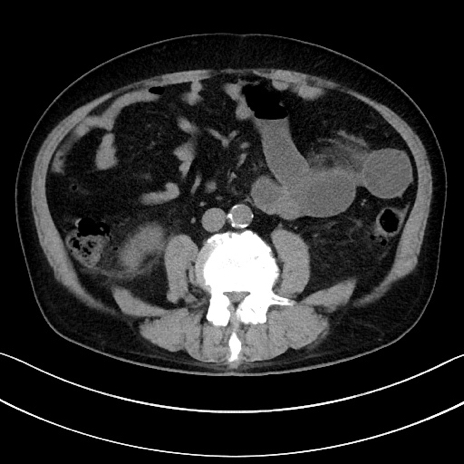

症例15(横断像)

【症例】70歳代男性

【主訴】腹痛

【現病歴】今朝から腹痛あり。全体的に痛い。特に左上の方。排ガスが今日はない。冷や汗が出る。

【既往歴】直腸癌術後

【身体所見】左側腹部〜上腹部に圧痛あり。腹膜刺激症状明らかなではない。軽度反跳痛。左下腹部に術後瘢痕あり。

【データ】WBC 7700、CRP 0.02